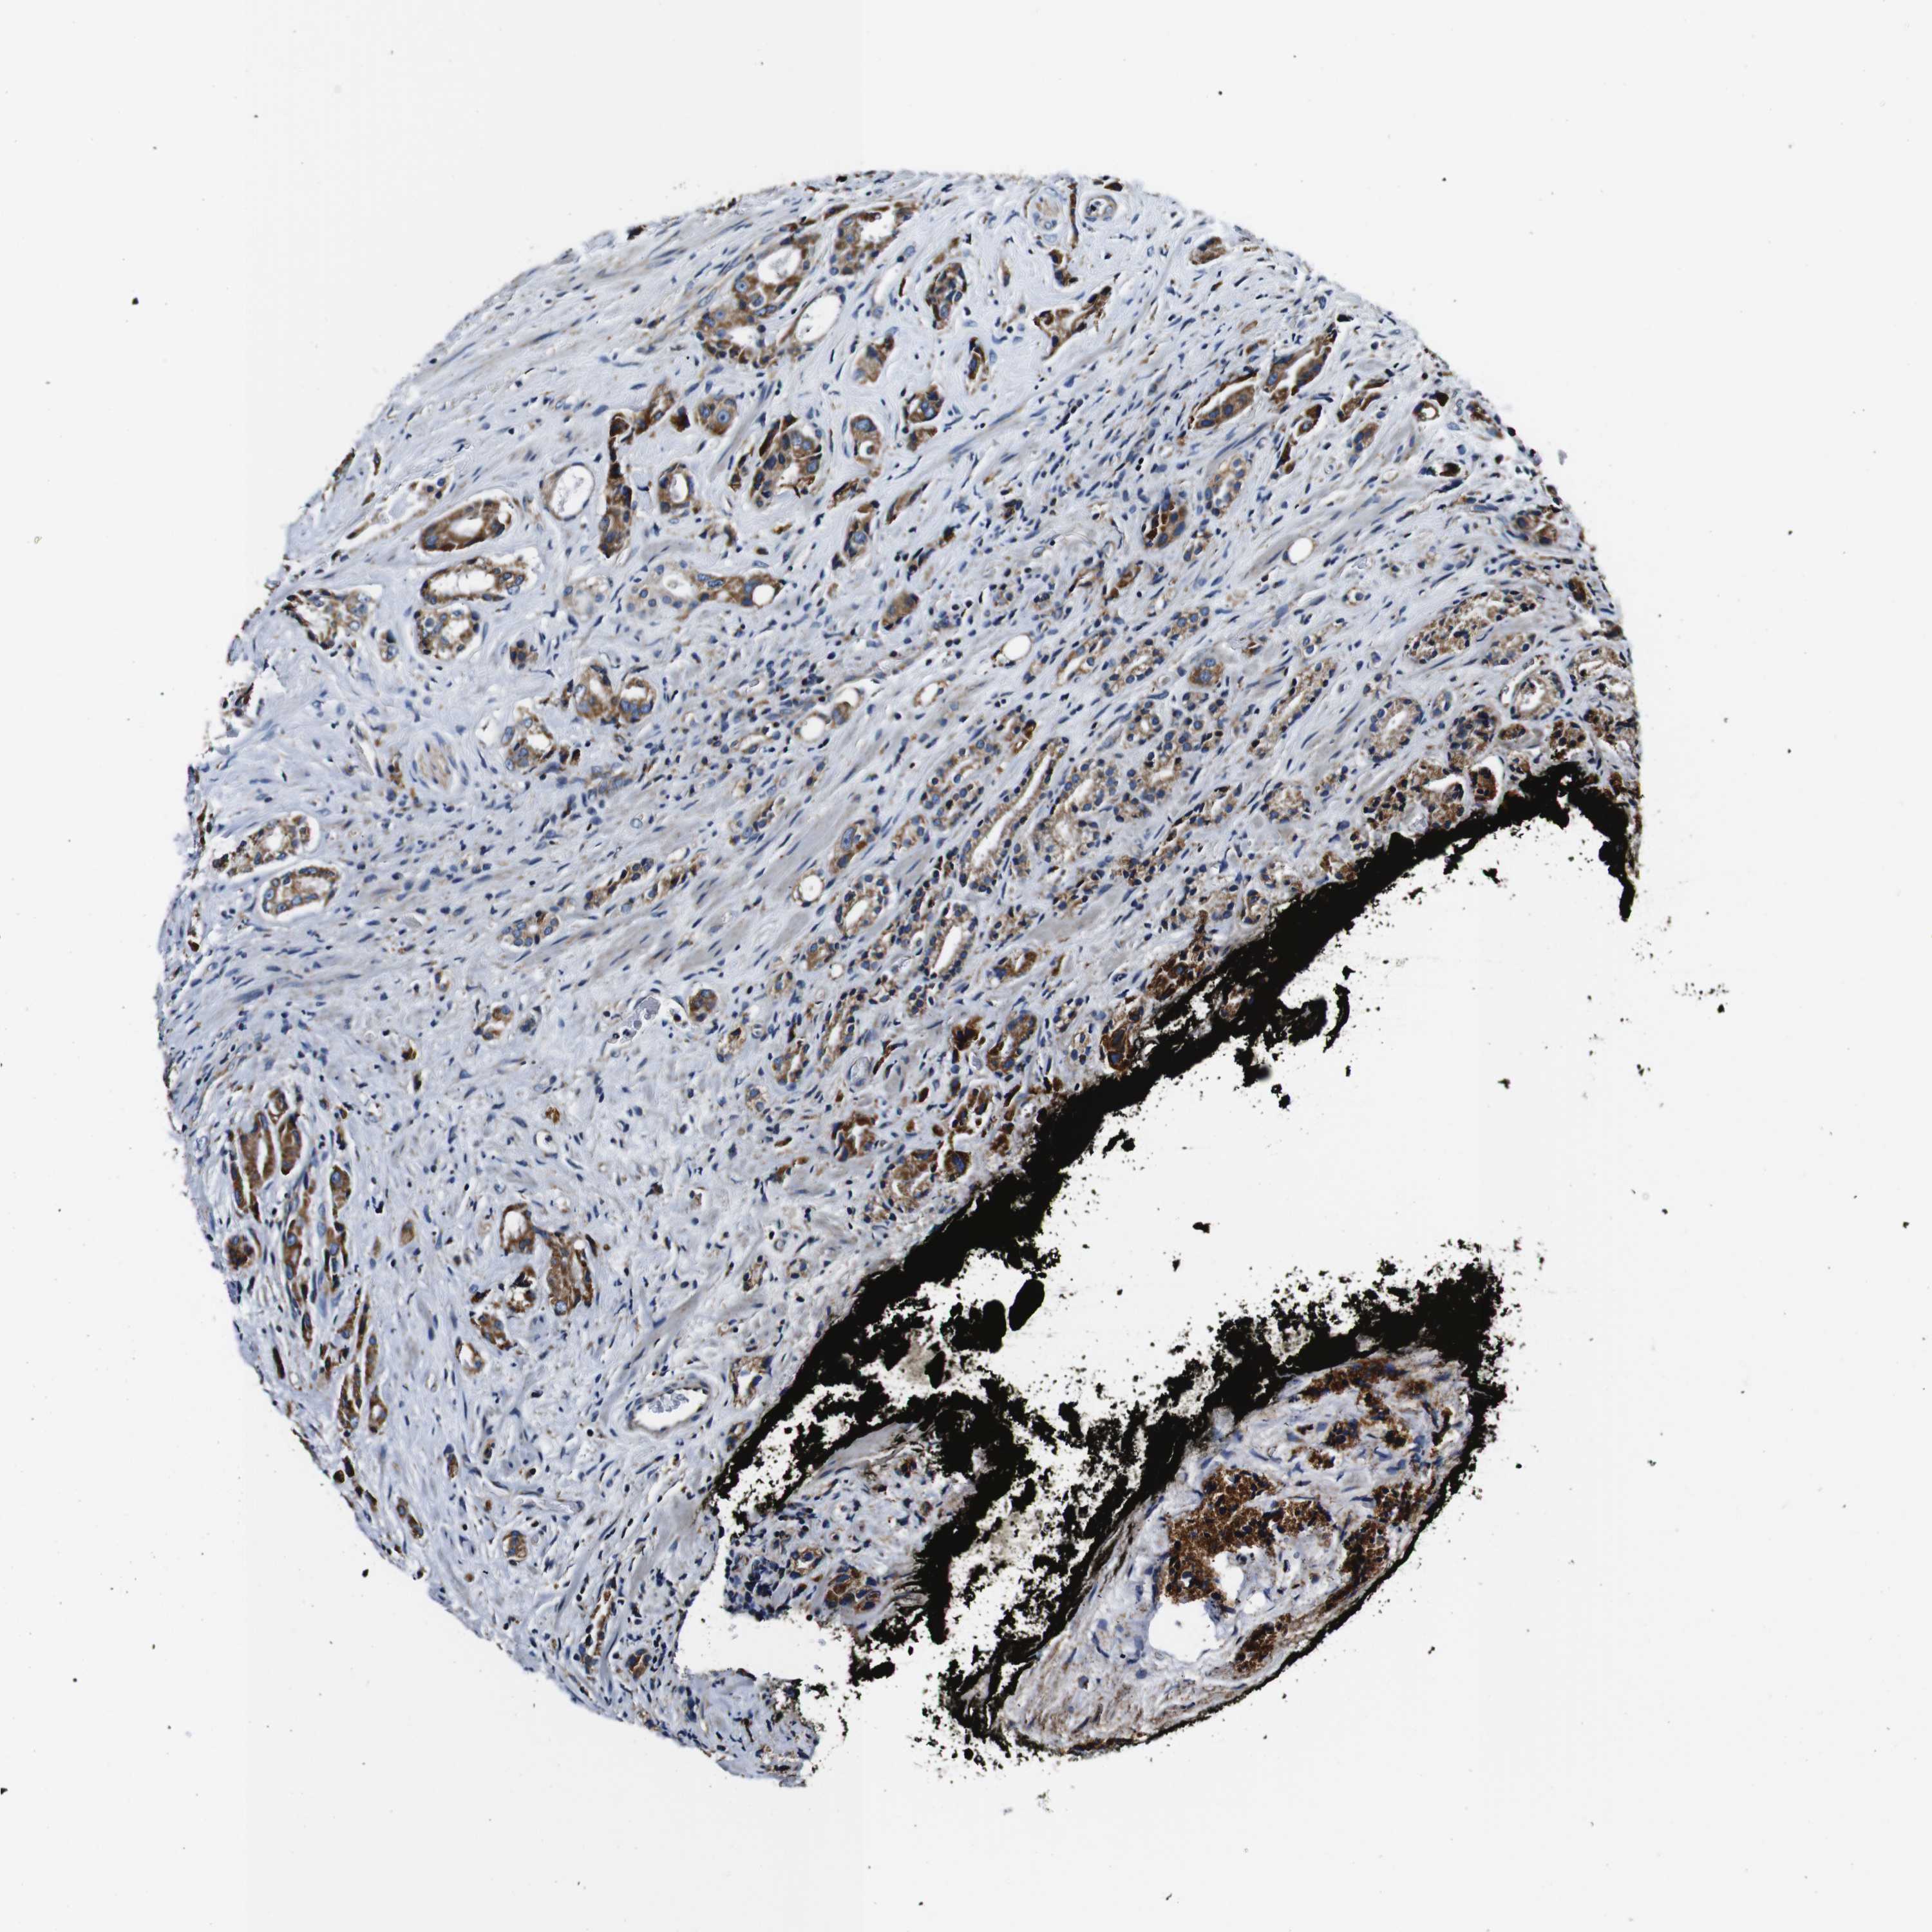

PROSTATE CANCER - Protein expressioni

A mouse-over function shows sample information and annotation data. Click on an image to view it in a full screen mode. Samples can be filtered based on level of antibody staining by selecting one or several of the following categories: high, medium, low and not detected. The assay and annotation is described here.

Antibody stainingi

Antibody staining in the annotated cell types in the current human tissue is reported as not detected, low, medium, or high, based on conventional immunohistochemistry profiling in selected tissues. This score is based on the combination of the staining intensity and fraction of stained cells.

Each image is clickable and will lead to virtual microscopy that enables deeper exploration of all samples and also displays staining intensity scores, fraction scores and subcellular localization as well as patient and tissue information for each sample.

Antibody HPA007043

Antibody HPA007044

Antibody CAB010052

Staining

High

Medium

Low

Not detected

Intensity

Strong

Moderate

Weak

Negative

Quantity

>75%

75%-25%

<25%

None

Location

Nuclear

Cytoplasmic/membranous

Cytoplasmic/membranous,nuclear

Adenocarcinoma, Low grade

Adenocarcinoma, High grade